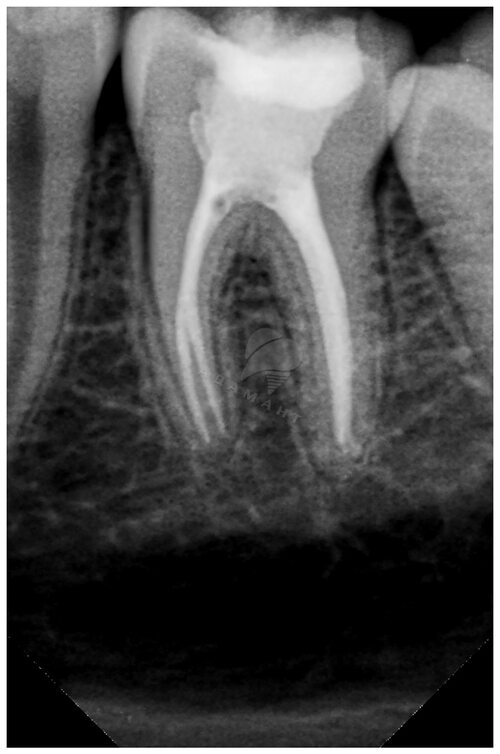

Если вам интересно узнать, как выглядят зубы без нерва, ниже представлены фотографии, которые помогут вам визуализировать процесс удаления нерва из зубов. Обратите внимание, что данные фотографии могут быть не рекомендованы для просмотра людям со слабой нервной системой.

Удаление нерва из зуба — хирургическая процедура, которая проводится в случае, когда нерв становится поврежденным или воспаленным. Врач-стоматолог проводит анестезию, затем делает доступ к зубу и удаляет нерв, очищая его каналы. После этого каналы заполняются специальным материалом, чтобы предотвратить возможное воспаление.

После удаления нерва из зуба, он может стать более хрупким и подверженным повреждениям. Поэтому врач-стоматолог может рекомендовать дополнительные процедуры, такие как установка стоматологической коронки или пломбирование, чтобы укрепить и защитить зуб от последствий удаления нерва.